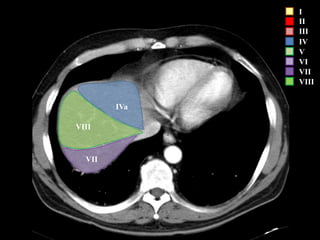

COUINAUD asignó un sistema de numeración para definir la segmentación

hepática.

I

II

III

IV

V

VI

VII

VIII

IVa

I – Entre cava y porta

II – el más superior de los izquierdos

III – Por debajo del II

IV – por delante de la vesícula

V – por detrás de la vesícula

VI – relación con riñón derecho

VII – el más posterior de los segmentos superiores

VIII – domo hepático

Las claves de la segm. Hepática